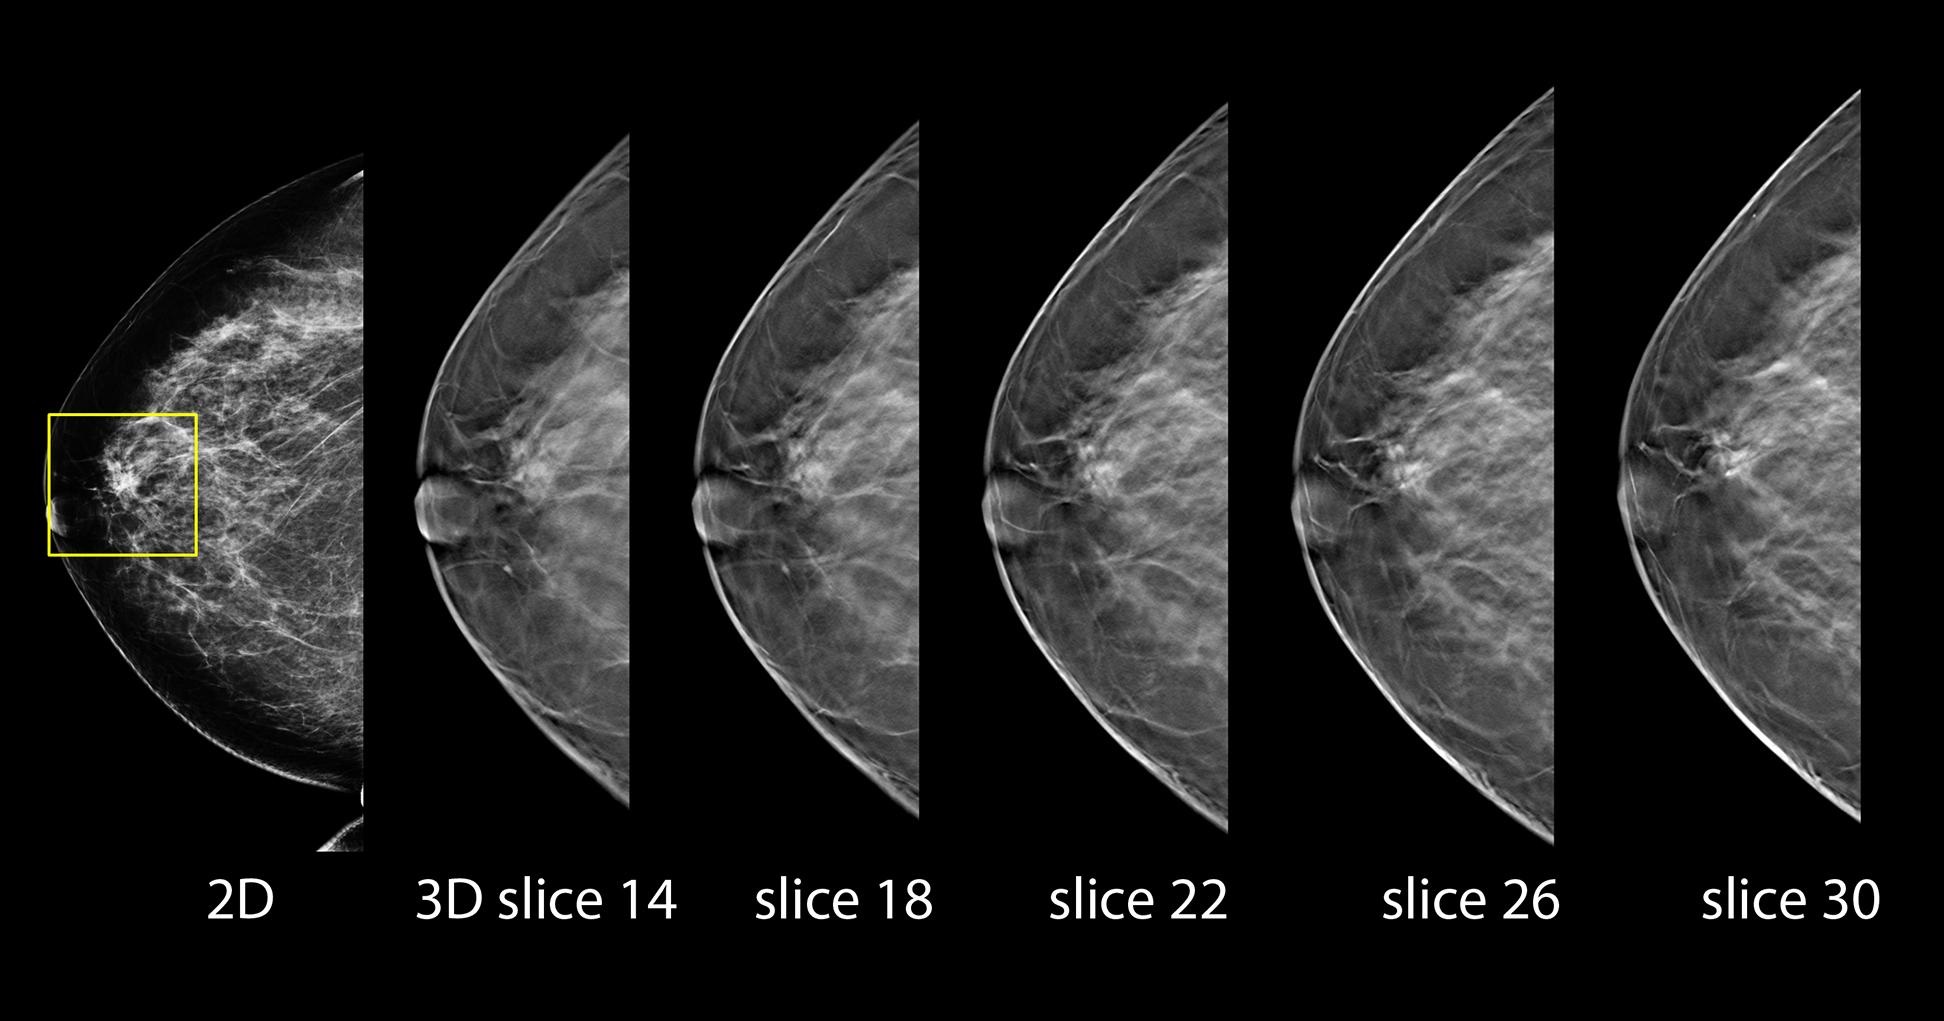

Comparison of 2D and 3D Mammography.

Breast cancer is challenging to prevent due to its complex causes, so the emphasis should be on early detection and treatment. Currently, mammography is the most effective breast cancer screening tool recommended by international research, as it can detect small, hidden lesions. Traditionally, mammography used 2D technology, but continuous advancements have significantly improved breast imaging.

3D mammography has recently emerged as a new trend in breast cancer screening. This imaging technology offers more detailed images, helping doctors make more accurate diagnoses.

To illustrate, 2D mammography is like looking at a book with all the pages stacked together, while 3D mammography allows doctors to examine breast tissue page by page. By capturing images from multiple angles and reconstructing them into a 3D dynamic image, doctors can better inspect each layer of breast tissue and locate hidden lesions. Although 3D mammography still requires compression to reduce breast thickness and enhance diagnostic accuracy, the technology can shorten the duration of compression and minimise discomfort.